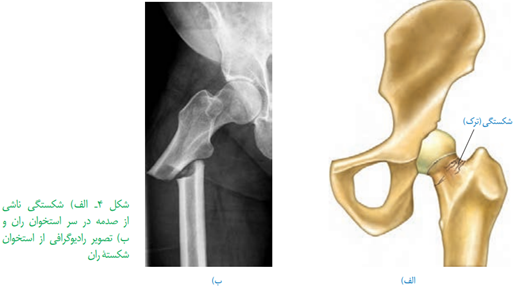

•استخوان های بدن به طور پیوسته دچار شکستگی های میکروسکوپی میشوند که نتیجه حرکات معمول بدن اند. شکستگی های دیگر میتوانند ناشی از ضربه یا برخورد باشند. در این حالت،یاخته های نزدیک به محل شکستگی، یاخته های جدید استخوانی می سازند و پس از چند هفته آسیب بهبود پیدا میکنند.